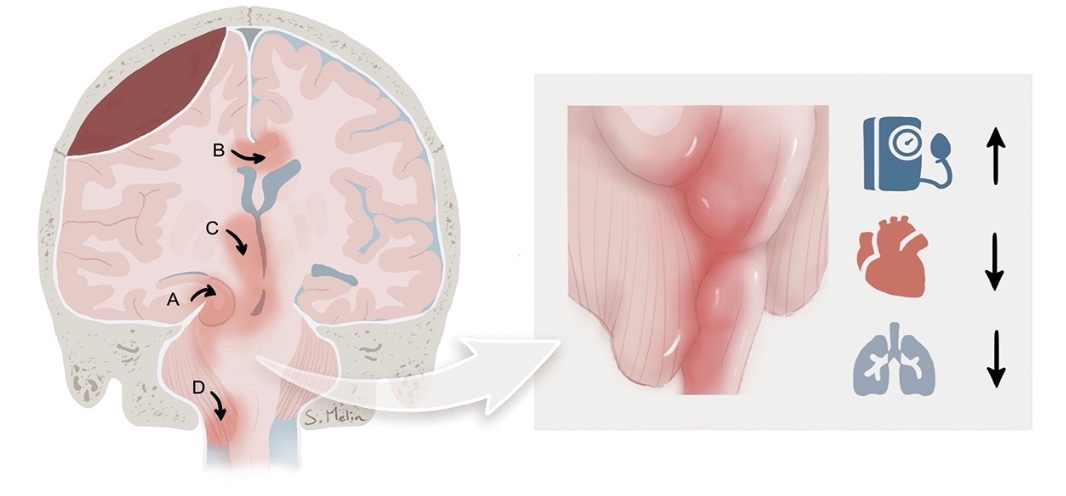

Stereotaktisk neurokirurgi inbegriper normalt att en stereotaktisk ram fästs på utsidan av skallbenet (tabula externa) med fyra skruvar. En DT/MR-låda fästs på ramen, och efter radiologisk undersökning erhåller man ett kartesiskt koordinatsystem och kan via ett borrhål föra in elektroder till centrala delar av hjärnan med millimeterprecision. Den första stereotaktiska ramen för människor introducerades 1947, och stereo­taktiska lesioner, framför allt pallidotomi och talamotomi, var före introduktionen av levodopa i slutet av 1960-talet den enda säkra och effektiva behandlingen mot motoriska besvär av Parkinsons sjukdom [1]. Mot slutet av 1980-talet utvecklades djup hjärnstimulering [2, 3], som innebär att stereotaktiskt inlagda hjärn­elektroder kopplas till en stimulator under huden på bröstkorgen. Denna kan därefter programmeras med en extern enhet så att de patologiska signaler som ger upphov till patientens symtom störs ut (Figur 1). De vanligaste anatomiska målen för djup hjärnstimulering är nucleus subthalamicus vid Parkinsons sjukdom, ventrolaterala talamus vid essentiell tremor och globus pallidus internus vid dystoni. Den stora fördelen med djup hjärnstimulering jämfört med tidigare lesionella metoder är att man säkrare kan utföra bilateralt ingrepp, som ofta är nödvändigt vid till exempel Parkinsons sjukdom och dystoni [4]. Behandlingen är komplex, livslång och ställer stora krav på en bred kompetens, varför behandlingen ges av multidisciplinära team. Djup hjärnstimulering  övervägs vid Parkinsons sjukdom hos patienter i komplikationsfas och ökar tiden som patienten befinner sig i sitt bästa motoriska tillstånd (så kallad »good on«-tid), utan tremor, brady- eller hyperkinesier [5]. Djup hjärnstimulering  är i dag en etablerad och evidensbaserad behandling, som enligt Socialstyrelsens nationella riktlinjer för Parkinsons sjukdom ska utgöra förstahandsvalet bland de avancerade behandlingarna [5]. Trots detta skiljer sig Sverige något från andra länder i EU genom att den vanligaste indikationen för djup hjärnstimulering inte är Parkinsons sjukdom utan essentiell tremor. Orsaken är förstås multifaktoriell, men delvis avspeglas detta i att färre av de lämpade patienterna med Parkinsons sjukdom får djup hjärnstimulering i Sverige till förmån för läkemedelspumpar eller fortsatt eventuellt ineffektiv läkemedelsbehandling.

Figur 1. Robotassisterad stereotaktisk inläggning av elektrod för djup hjärnstimulering.